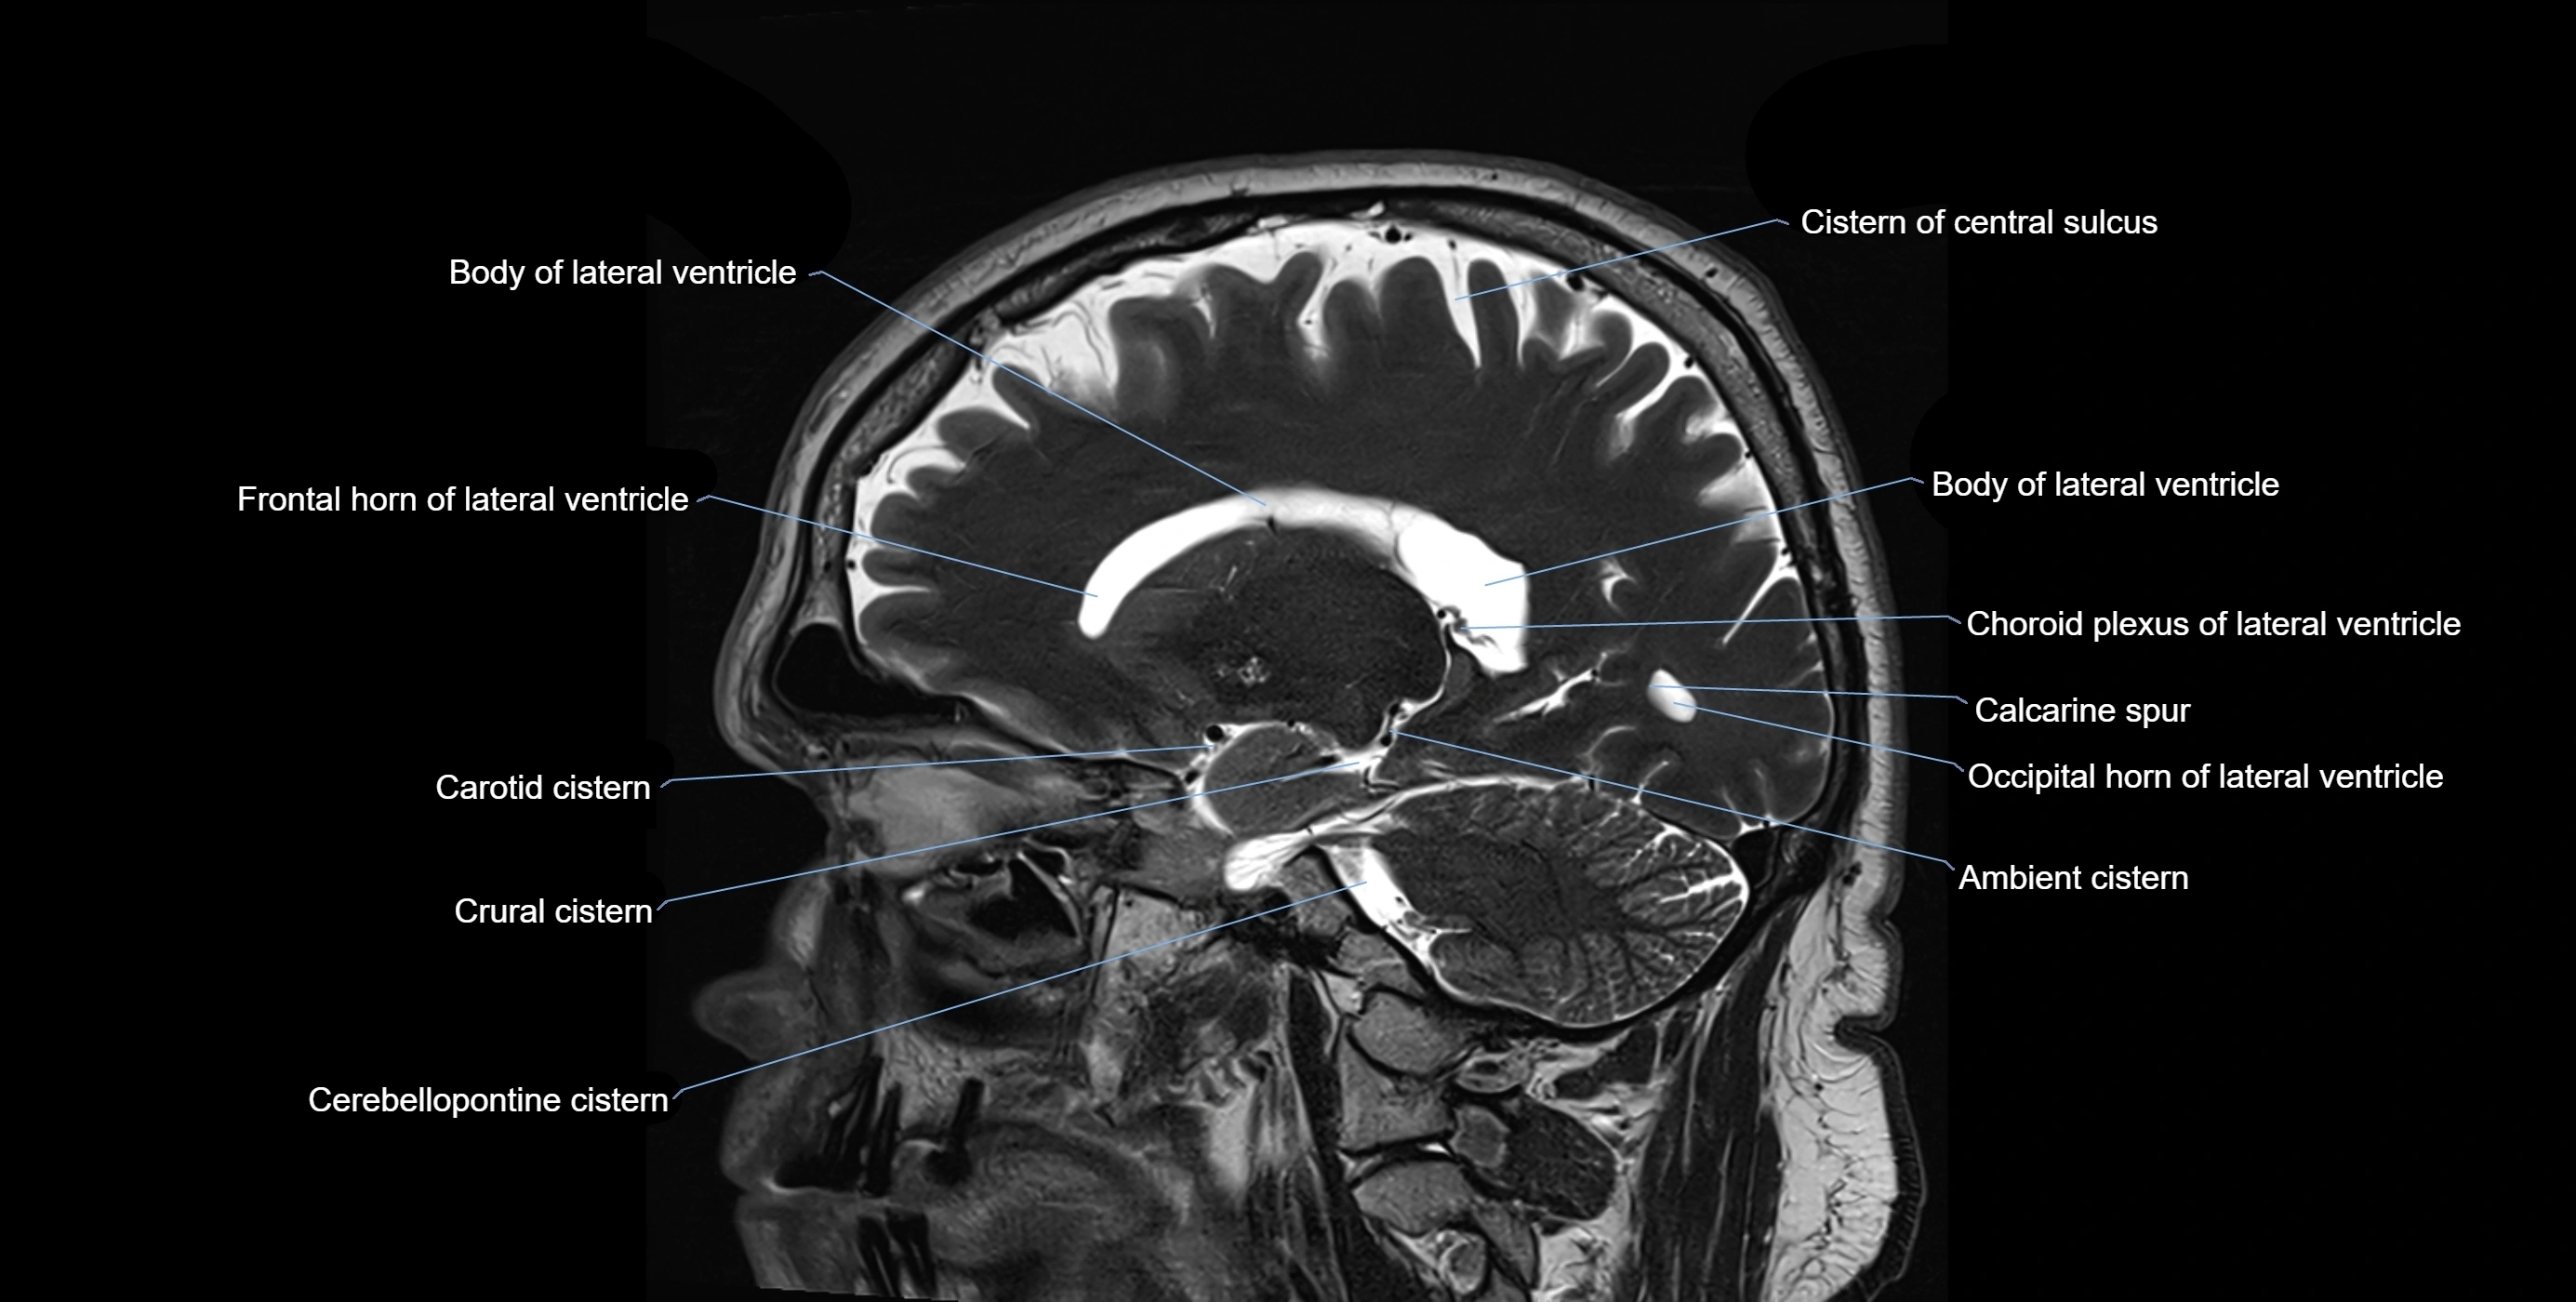

MRI images

image